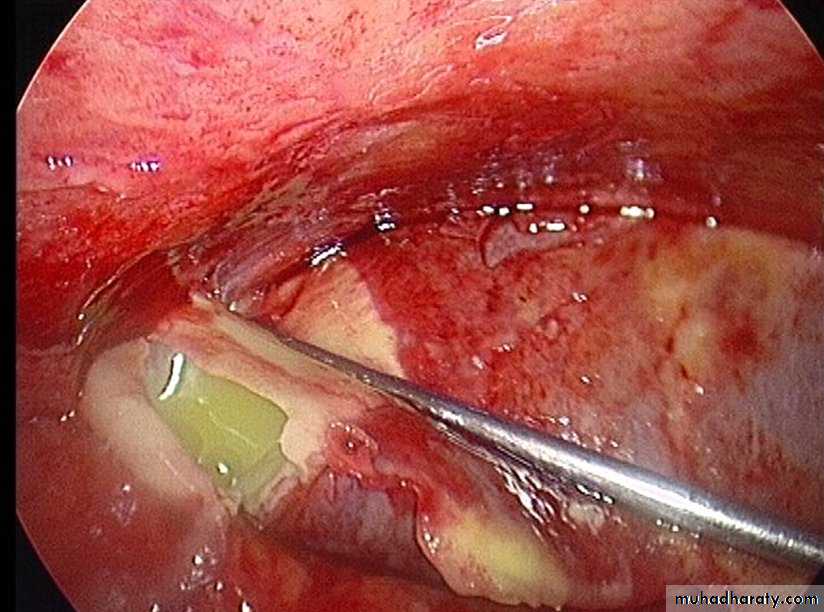

The pelvis is the commonest site of an intraperitoneal abscess because the vermiform appendix is often pelvic in position and the fallopian tubes are frequent sites of infection. A pelvic abscess can also occur as a sequel to any case of diffuse peritonitis and is common after anastomostic leakage following colorectal surgery. The most characteristic symptoms are diarrhea and the passage of mucus in the stools. Rectal examination reveals a bulging of the anterior rectal wall, which, when the abscess is ripe, becomes softly cystic. Left to nature, a proportion of these abscesses burst into the rectum, after which the patient nearly always recovers rapidly. If this does not occur, the abscess is definitely pointing into the rectum, rectal drainage (Fig. 58.6) is employed. If any uncertainty exists, the presence of pus should be confirmed by ultrasound or CT scanning with needle aspiration if indicated. Laparotomy is almost never necessary. Rectal drainage of a pelvic abscess is far preferable to suprapubic drainage, which risks exposing the general peritoneal cavity to infection. Drainage tubes can also be inserted percutaneously or via the vagina or rectum under ultrasound or CT guidance .Al-Madena copy